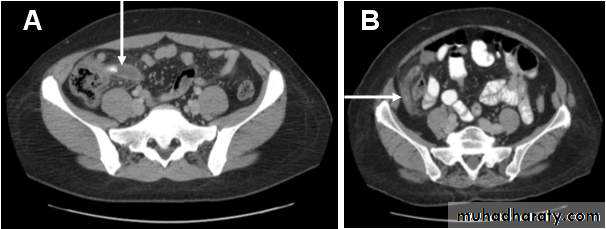

CT findings of acute appendicitis:

• CT shows a swollen appendix.

• Soft tissue stranding pattern in adjacent Fat. This stranding pattern is a highly useful sign on

• CT indicating edema in fat adjacent to inflammation.

• Large fecoliths at the base of the appendix.

• Complication: abscess, inflammatory mass.